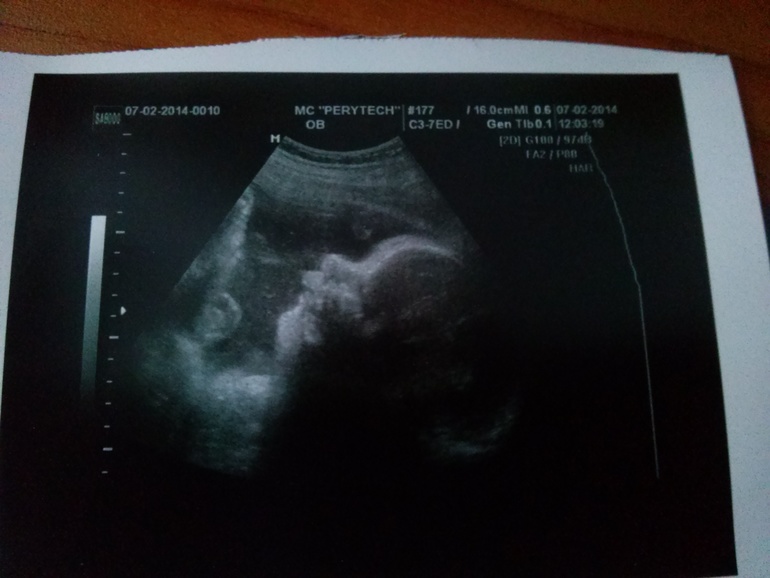

сходили на плановое узи!)

Ходили с папой))короче чтобы долго не рассказывать,в заключении все норм НО поставили умеренное многоводие:(

Весим мы 2460,рост 44 вот большинькие уже какие,пдр еще позже поставили,думаю не дохожу!